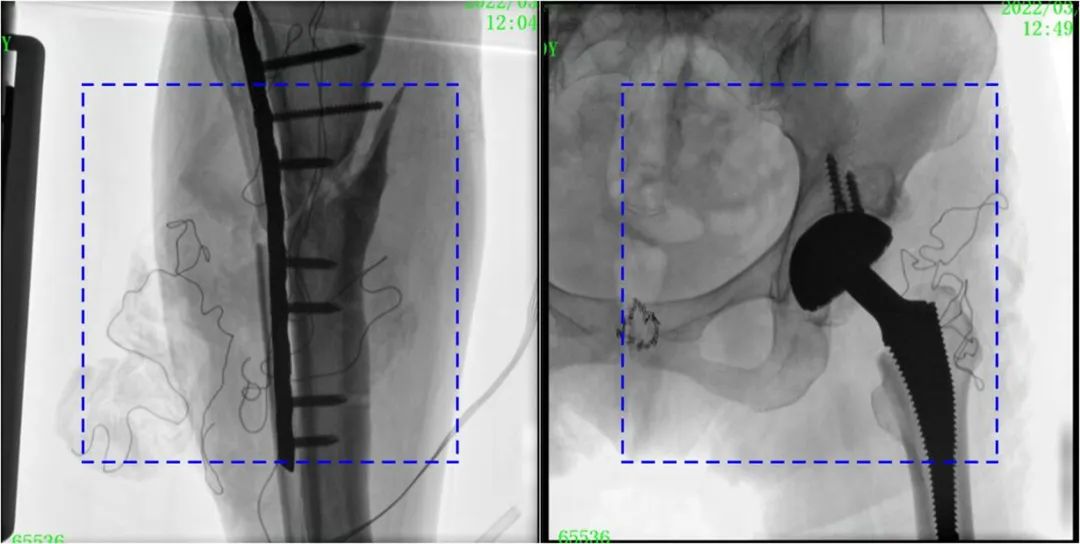

術(shù)中定位準(zhǔn)確、出血量少,術(shù)后影像顯示股骨移位糾正,恢復(fù)良好力線,手術(shù)效果良好。

PLX119C臨床圖像與傳統(tǒng)圖像對(duì)比

注:藍(lán)色虛線內(nèi)為傳統(tǒng)21CM×21CM平板的成像區(qū)域。